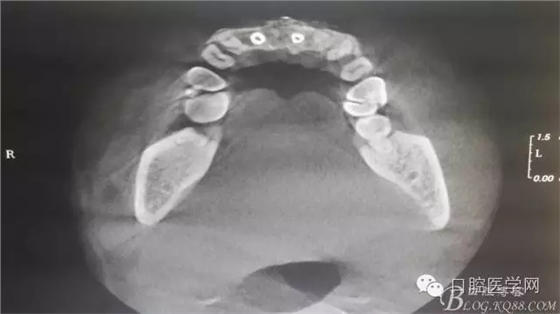

半年后...

遺憾沒(méi)有保留術(shù)前口內(nèi)照片,只有術(shù)后的。

后期的修復(fù)工作由之前的轉(zhuǎn)診醫(yī)生后續(xù)處理,由于GBR過(guò)程骨膜減張導(dǎo)致角化牙齦不足3mm,建議角化牙齦移植改變其更好的牙齦生物型。